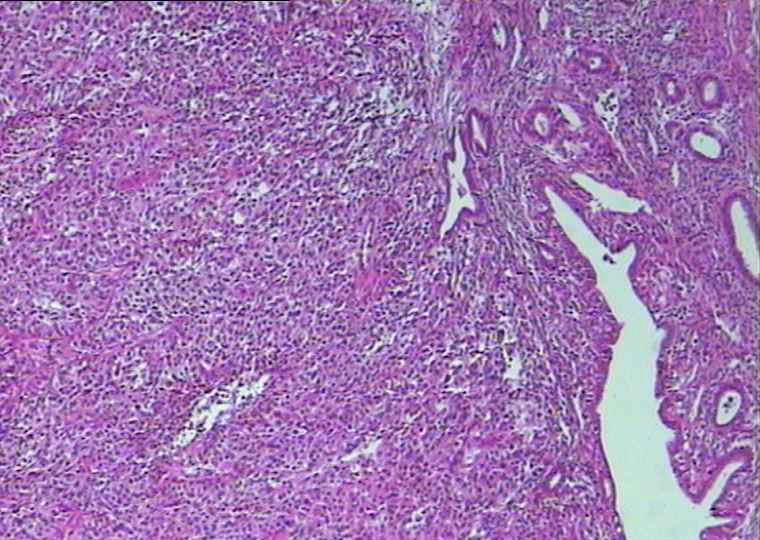

女,56岁

宫腔内淡黄色隆起型肿物数枚,实性质软,直径1.5~3cm,其一侵及浆膜面,肿物累及颈管及一侧输卵管,卵巢,并在输卵管膨大处形成直径0.5cm淡黄色菜花样肿物。

个人倾向高级别浆乳癌,看看大家的意见